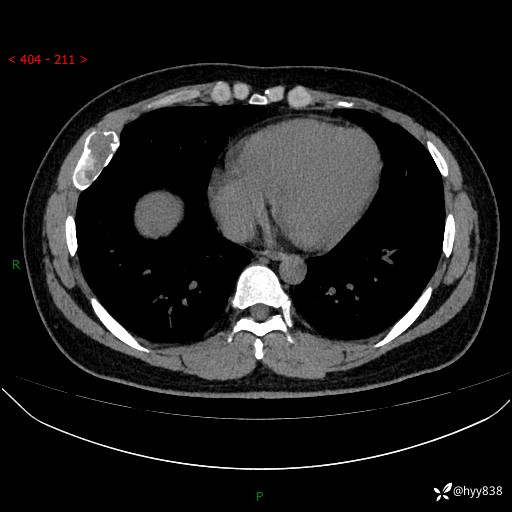

胸部CT平扫